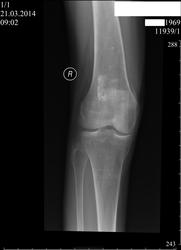

Как можно расценить обызвествление в метадиафизе бедренной кости? За счёт какого субстрата это обызвествление?Обызвествление костного мозга? Или что-то другое?

Думаю кальцинация костного мозга, после травмы такое бывает

Более вероятно, последствия инфаркта кости

Никто и энхондрому не исключит.